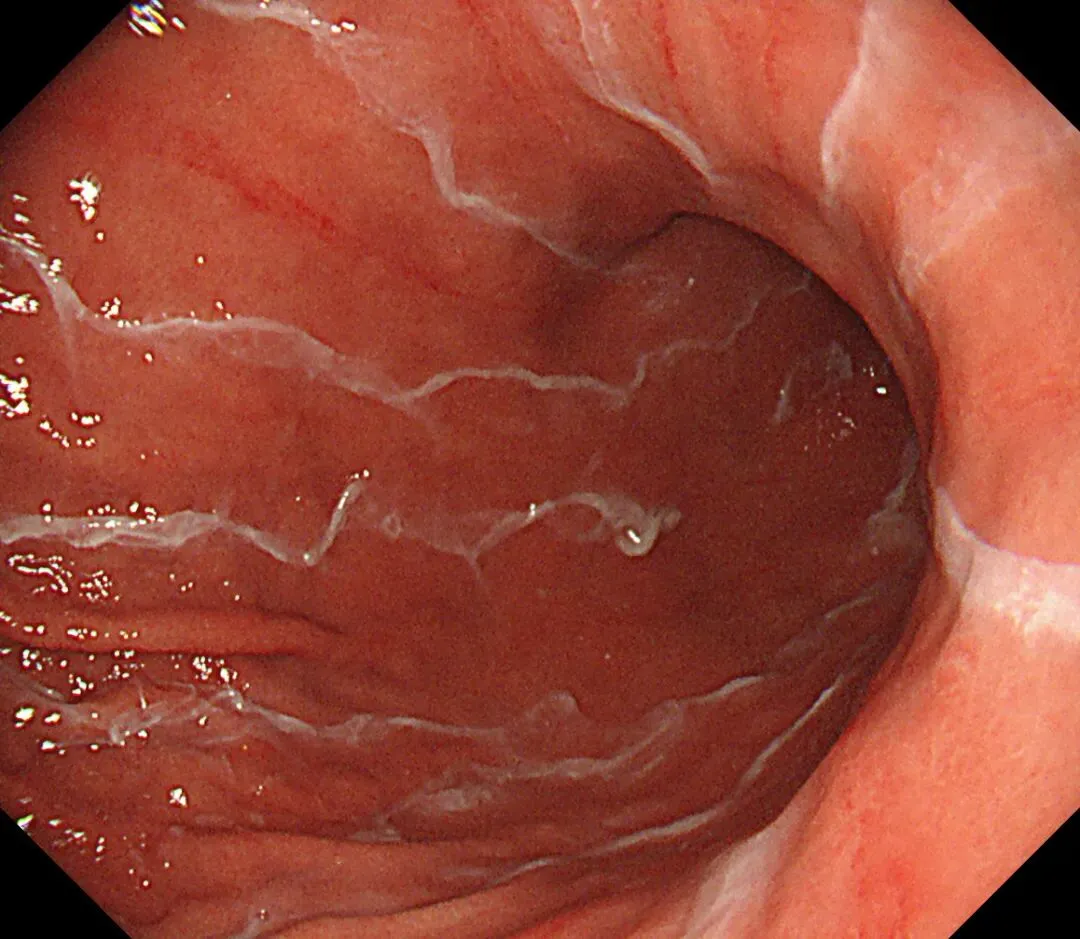

顽固性黏液(sticky adherent dense mucus):多呈灰黄色、黄白-乳白色,黏稠度高,附着于胃壁不易剥离,强行去除容易出血,也常有人称之为酒糟样固形物,多见于自身免疫性胃炎(AIG)进展期患者。

顽固性黏液case1,确诊为A型胃炎患者👇